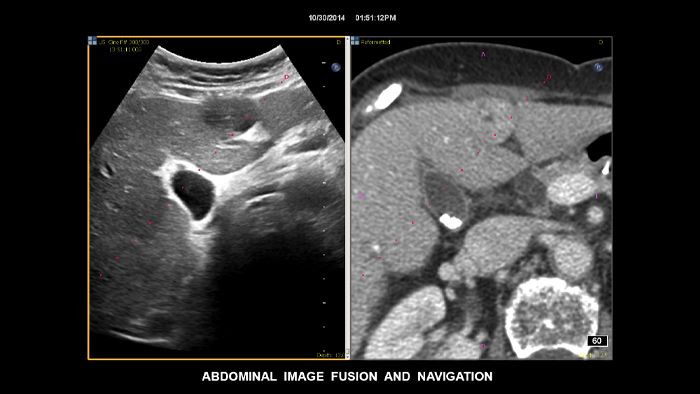

Treffen Sie auch in diagnostisch schwierigen Fällen die richtige Entscheidung mit den Philips Funktionen zur Bildfusion und Nadelnavigation. Ein effizienter Arbeitsablauf ermöglicht Klinikteams eine schnelle und effektive Fusion von CT/MRT/PET mit Live-Ultraschallbildern, wobei die Nadelnavigation die Biopsieführung bei kleinen, schwer zugänglichen Läsionen unterstützt.³